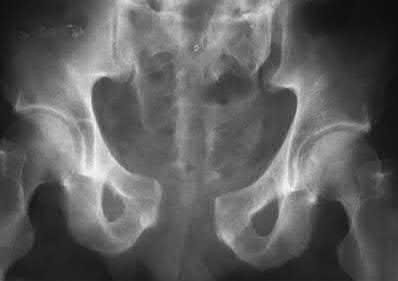

Question 11:

A poly-trauma patient presents hemodynamically unstable with an anteroposterior compression (APC-III) pelvic ring injury. A circumferential pelvic binder is requested to reduce pelvic volume and control hemorrhage. To be anatomically effective, the binder must be centered precisely over which of the following landmarks?

Correct Answer: Greater trochanters

Explanation:

For optimal mechanical advantage and effective reduction of an 'open book' pelvic fracture (APC type), a pelvic binder must be applied directly over the greater trochanters of the femurs. Applying it higher, such as over the iliac crests, is a common error that fails to adequately close the pelvic ring and can paradoxically open the true pelvis.